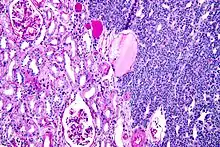

Micrograph of a metanephric adenoma with structures reminiscent of those seen in papillary renal cell carcinoma. H&E stain.

Metanephric adenoma (MA) is a rare, benign tumour of the kidney, that can have a microscopic appearance similar to a nephroblastoma (Wilms tumours),[1] or a papillary renal cell carcinoma.

Metanephric adenoma is diagnosed histologically. The tumours can be located at upper pole, lower pole and mid-hilar region of the kidney; they are well circumscribed but unencapsulated, tan pink, with possible cystic and hemorrhagic foci. They show a uniform architecture of closely packed acinar or tubular structures of mature and bland appearance with scanty interposed stroma.[3][4][5][6][7] Cells are small with dark staining nuclei and inconspicuous nucleoli. Blastema is absent whereas calcospherites may be present. Glomeruloid figures are a striking finding, reminiscent of early fetal metenephric tissue. The lumen of the acini may contain otherwise epithelial infoldings or fibrillary material but it is quite often empty. Mitoses are conspicuously absent.[3][4][5][6][7] In the series reported by Jones et al. tumour cells were reactive for Leu7 in 3 cases of 5, to vimentine in 4 of 6, to cytocheratin in 2 of 6, to epithelial membrane antigen in 1 of 6 cases and muscle specific antigen in 1 of 6.[5] Olgac et al. found that intense and diffuse immunoreactivity for alpha-methylacyl-CoA racemase (AMACR) is useful in differentiating renal cell carcinoma from MA but a panel including AMACR, CK7 and CD57 is better in this differential diagnosis.[8] Differential diagnosis may be quite difficult indeed as exemplified by the three malignancies initially diagnosed as MA that later metastasized, in the report by Pins et al.[9]